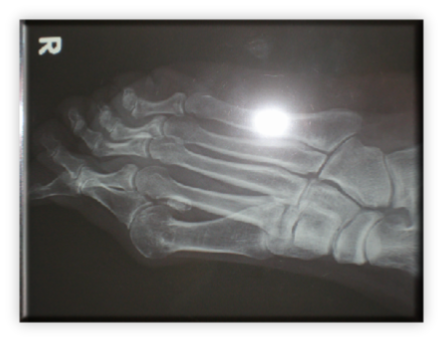

Πρόκειται για σύνθετη παθολογία του μεγάλου δακτύλου του ποδιού, που εκτός από την παραμόρφωση σε βλαισσότητα, όπως το όνομα υποδηλώνει, συνυπάρχει στροφική παραμόρφωση και γενικότερα παραμόρφωση ολόκληρου του πρώτου στοίχου (ταρσός, μετατάρσιο, δάκτυλο) αλλά και των μικρότερων δακτύλων. Πιο συγκεκριμένα, υπάρχουν οστεόφυτα στις αρθρώσεις και κυρίως στην έσω επιφάνεια της κεφαλής του πρώτου μεταταρσίου (κότσι), τροφικές αλλοιώσεις του δέρματος και δερματικοί κάλοι στα σημεία αυξημένης φόρτισης, λέπτυνση του υποδορίου λίπους στην πελματιαία επιφάνεια, εξάρθρημα σησαμοειδών οσταρίων, ανισορροπία στους άξονες έλξης των τενόντων περί του μεγάλου δακτύλου, υμενίτιδα στην έσω επιφάνεια της μεταταρσιοφαλλαγγικής η οποία είναι και πολύ επίπονη. Εμβιομηχανικά ο άξονας φόρτισης του ποδιού μεταφέρεται στο διάστημα μεταξύ πρώτου και δεύτερου στοίχου με αποτέλεσμα το πρώτο μετατάρσιο να δέχεται λιγότερα φορτία από όσο θα έπρεπε και τελικώς μεταταρσιαλγία στις κεφαλές των μικρότερων μεταταρσίων, παραμορφώσεις των μικρότερων δακτύλων με συχνότερη αυτή του δευτέρου που καταλήγει σε γαμψοδακτυλία, εφίππευση επί του πρώτου, στεόφυτα και δερματικό κάλο στην ραχιαία επιφάνεια της πρώτης φαλαγγοφαλαγγικής άρθρωσης, οστεοχόνδρινες αλλοιώσεις των αρθρώσεων και τελικά αρθρίτιδα.

ΒΛΑΙΣΟΣ ΜΕΓΑΛΟΣ ΔΑΚΤΥΛΟΣ (HALLUX VALGUS)

Στις ακτινογραφίες πρέπει να μετρηθούν η γωνία μεταξύ 1ου και 2ου μεταταρσίων με ανώτερα όρια 8-9 μοίρες, η γωνία βλαισσότητας του 1ου μεταταρσίου και 1ης φάλαγγας που όταν ξεπερνά τις 15 μοίρες ορίζεται παθολογική. Συμπληρωματικά μπορούν να μετρηθούν οι γωνίες προσανατολισμού της αρθρικής επιφάνειας κεφαλής 1ου μεταταρσίου και η γωνία προσανατολισμού κεντρικής αρθρικής επιφάνειας 1ης φάλαγγας του μεγάλου δακτύλου.